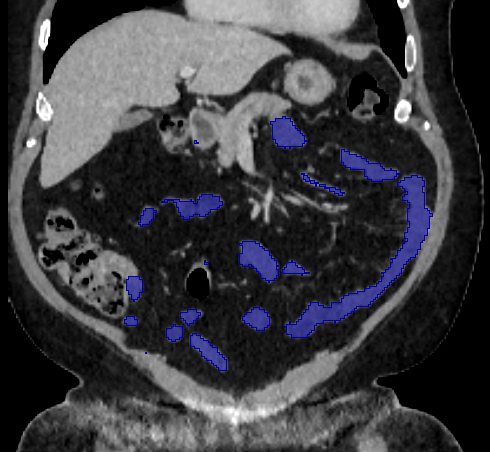

3.2 Qualitative Evaluation

Figure 3 shows example segmentation results in 3D. The result corresponding to ‘feat. & out. level DA’ in Table 1 is compared to ours. We note that the only difference between them is whether the feature disentanglement is involved for the domain adaptation, thus could show its effectiveness. Fewer errors are observed for the proposed method. We believe this is because the proposed method explicitly concentrates on the features more transferable across the datasets, the non-intensity features in this work, by disentangling those features and applying adversarial learning directly to them during the adaptation process. Example reconstruction results from the auto-encoding architecture as well as segmentation results in coronal view can be found in supplementary material.